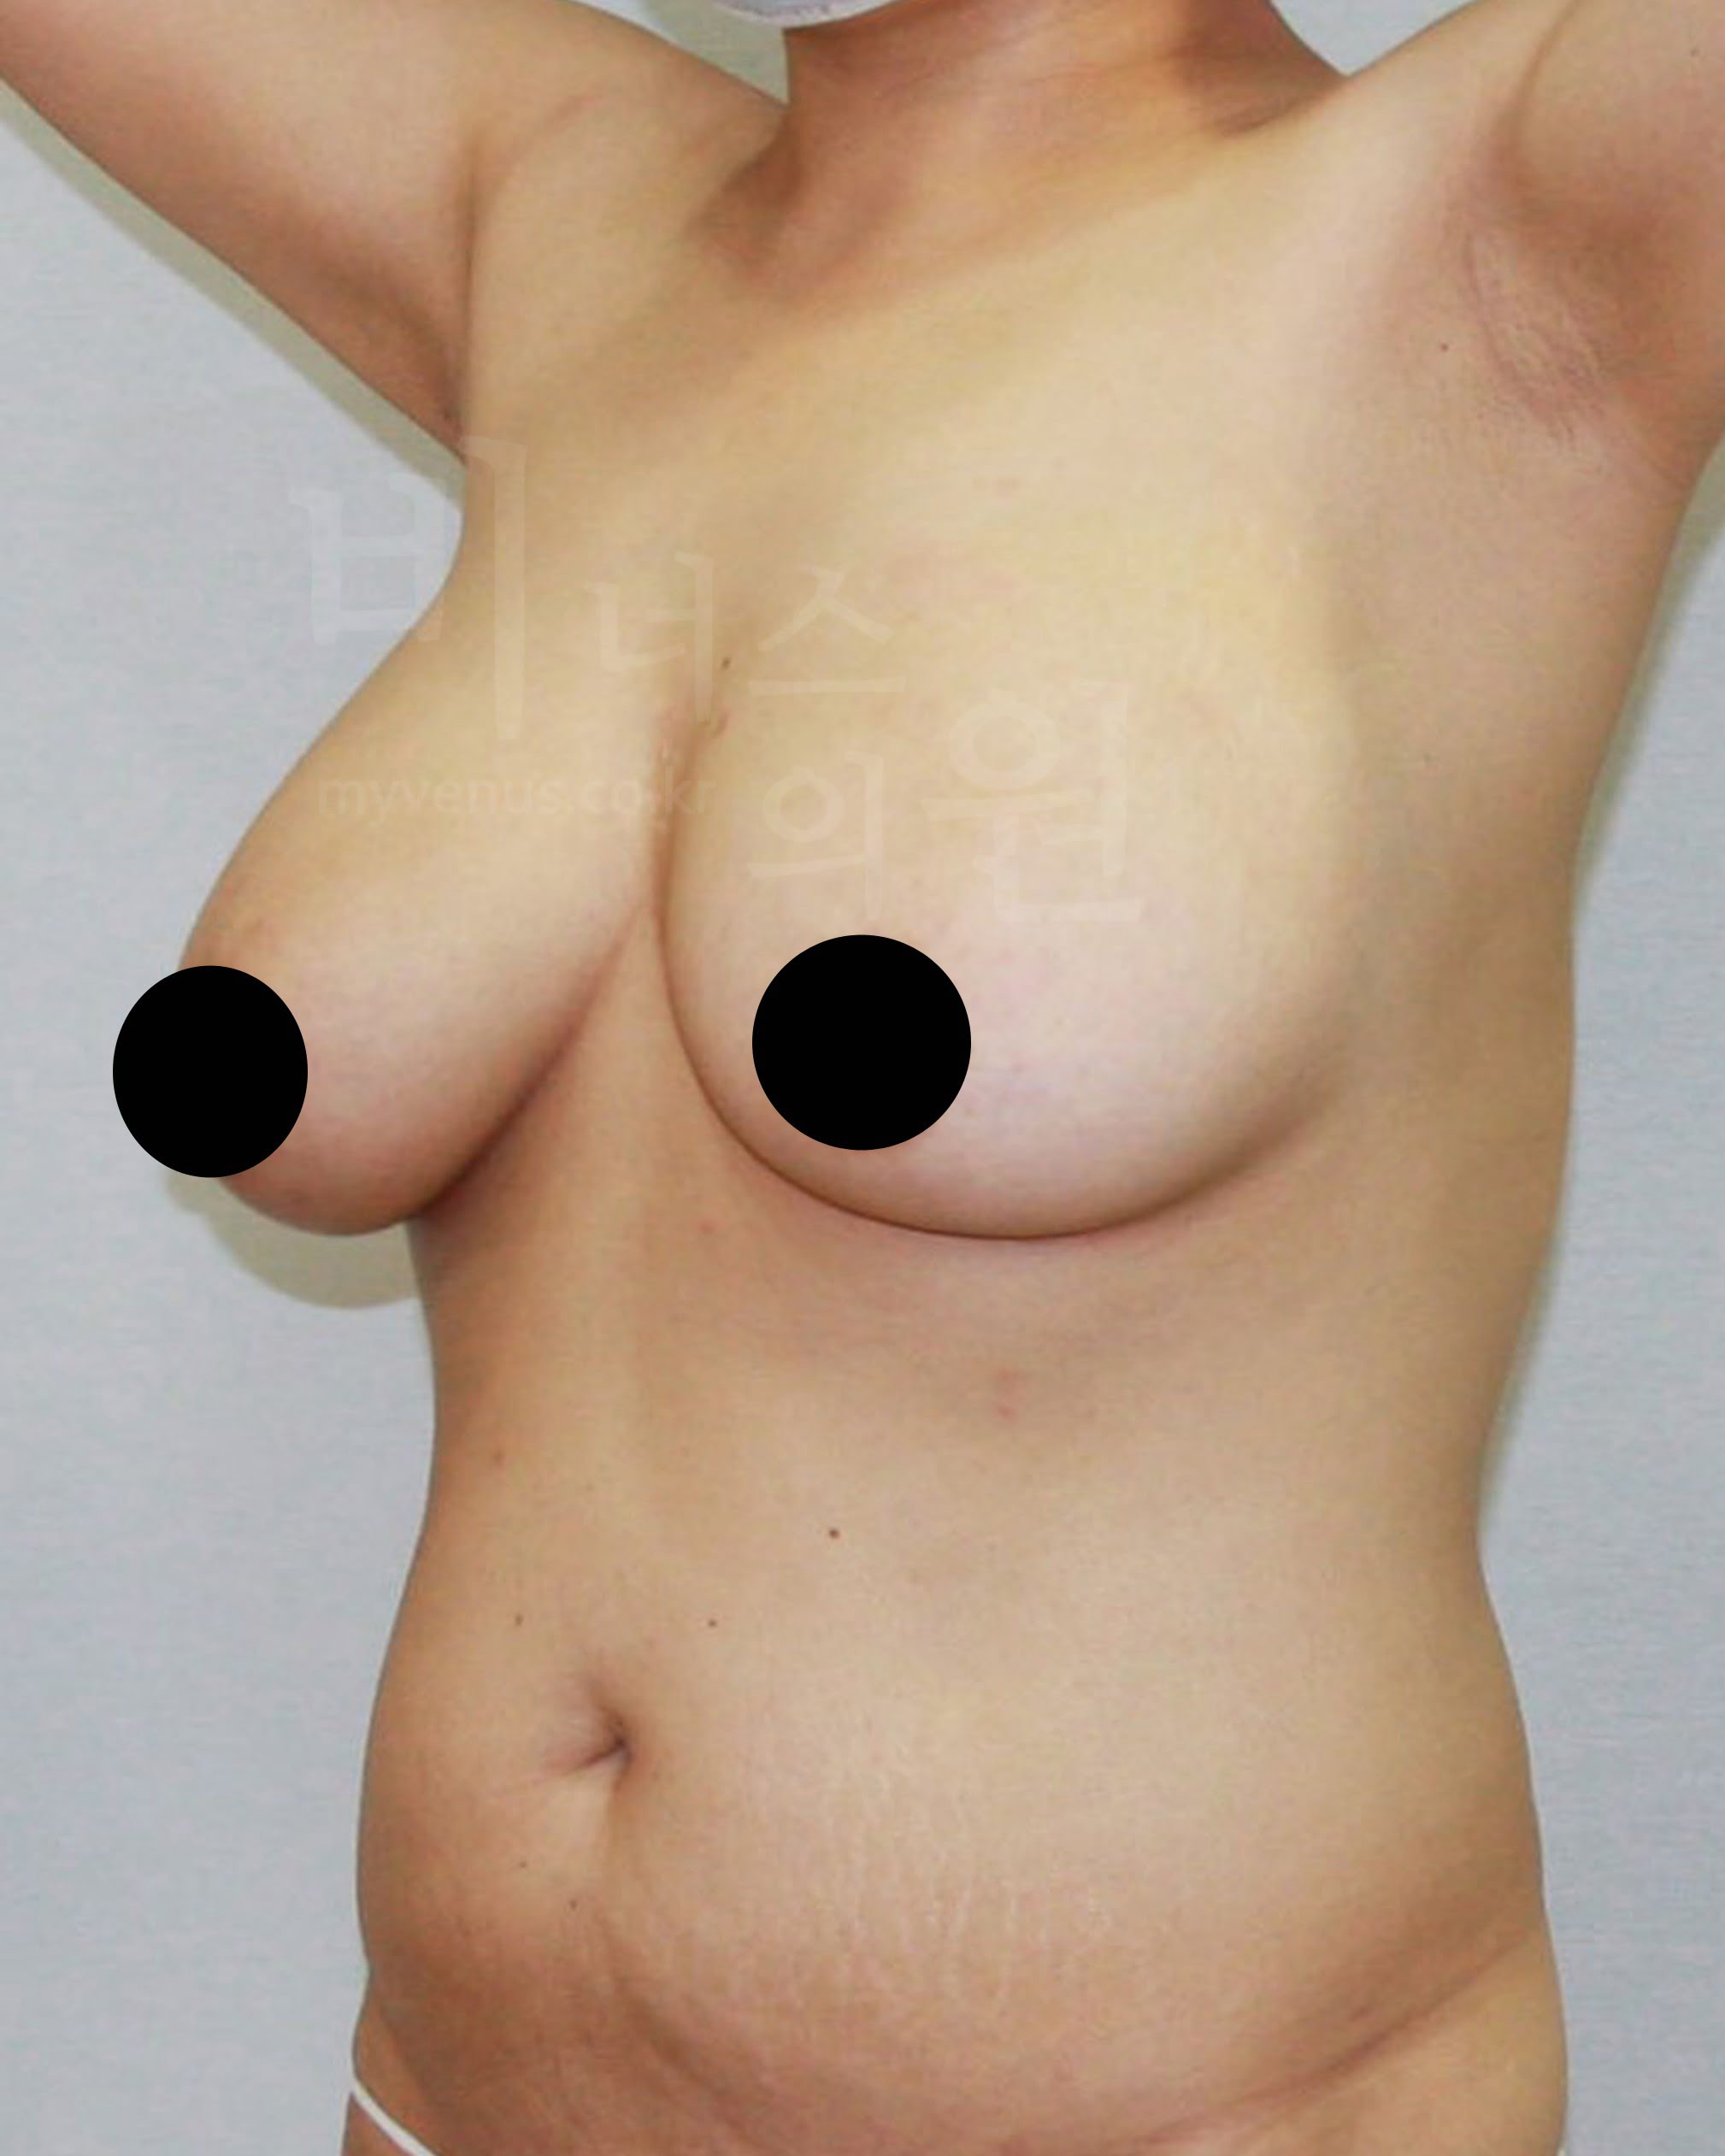

처지고 큰 가슴으로 무거움을 느끼셨고 일상생활의 불편함으로 내원해주신 50대의 여성분이세요. 최대의 사이즈 감소를 기대하셨어요. 가슴 전체 축소, 부유방, 겨드랑이, 유방 옆구리 지방흡입으로 처짐, 흉터 없이 사이즈 감소에 도움을 드리기로 했어요. 가슴 절개를 하지 않고도 많은 사이즈 감소가 이루어 졌어요.

팔뚝지방흡입 전 사진

굵은 팔뚝으로 상체가 더 커 보이는 모습

팔뚝지방흡입 후 사진

날씬한 팔뚝 변화로 상체도 슬림해 보이는 모습

가슴 전체가 탄력적이며, 유륜 절개 없이도 유륜축소와 처짐이 올라 갔어요. 가슴뿐만 아니라 부유방, 겨드랑이, 유방 옆구리 지방흡입으로 군살 제거와 함께 이어지는 라인의 균형감 있고 시원해 보여요.

길었던 유방선이 가슴축소로 짧아 졌어요. 지방흡입을 통해 안전하게 처짐과 가슴 사이즈가 개선되었어요. 미세한 흡입관을 사용하여 핸드메이드 마이크로 지방흡입으로 피부의 표면이 울퉁불퉁하지 않고 자연스러운 가슴의 모습이 되었어요.